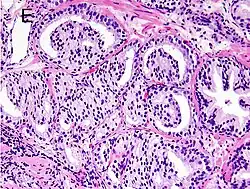

Cribriform pattern: Gleason grade 4

Gleason score 7 (3+4) with minor component of cribriform glands

Gleason 4

Gleason pattern 4 glands are no longer single/separated glands like those seen in patterns 1–3. They look fused together, difficult to distinguish, with rare lumen formation vs Gleason 1–3 which usually all have open lumens (spaces) within the glands, or can be cribriform-(resembling the cribriform plate/similar to a sieve: an item with many perforations). Fused glands are chains, nests, or groups of glands that are no longer entirely separated by stroma-(connective tissue that normally separates individual glands in this case). Fused glands contain occasional stroma giving the appearance of "partial" separation of the glands. Due to this partial separation, fused glands sometimes have a scalloped (think looking at a slice of bread with bite taken out of it) appearance at their edges.[4][7]